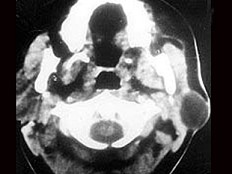

20.50歲女性患者,體檢發(fā)現(xiàn)右側(cè)甲狀腺有較硬結(jié)節(jié),CT掃描如圖所示,請(qǐng)選擇正確的描述和答案  (    )

正確答案:ABE